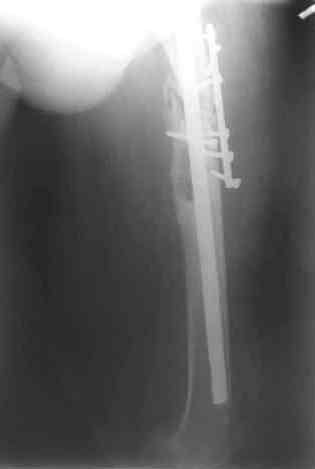

После нескольких некрэктомий, проведения аутодермопластики и заживдения ожоговой раны через 2 месяца после травмы произведен открытый остеосинтез левой бедренной кости штифтом и пластиной (деротационной) [image 01, 02]. Через 1 год и 7 месяцев после травмы у больного диагностированы ложный сустав и хронический остеомиелит левой бедренной кости. Произведено удаление металлических фиксаторов, секвестрэктомия и остеосинтез бедренной костивнешним двухплоскостным стержневым аппаратом [image 03, 04] .